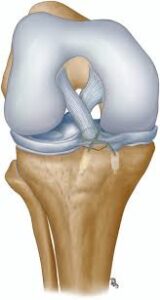

ACL avulsion fixation is a surgical procedure aimed at restoring stability and functionality to the knee joint following an anterior cruciate ligament (ACL) avulsion injury. An ACL avulsion occurs when the ligament tears away from its attachment point on the femur (thigh bone) or tibia (shin bone), often resulting from sudden trauma or excessive stress on the knee. ACL avulsion fixation involves reattaching the torn ligament to its anatomical insertion site using specialized techniques and fixation devices. Let’s delve into the details of ACL avulsion fixation, its surgical approach, and postoperative considerations.

The ACL is a crucial ligament that stabilizes the knee joint by preventing excessive forward movement of the tibia and rotational instability. An ACL avulsion injury occurs when the ligament is torn away along with a fragment of bone from its attachment point. This injury can lead to significant knee instability, pain, swelling, and functional limitations, particularly during activities involving cutting, pivoting, or sudden changes in direction.